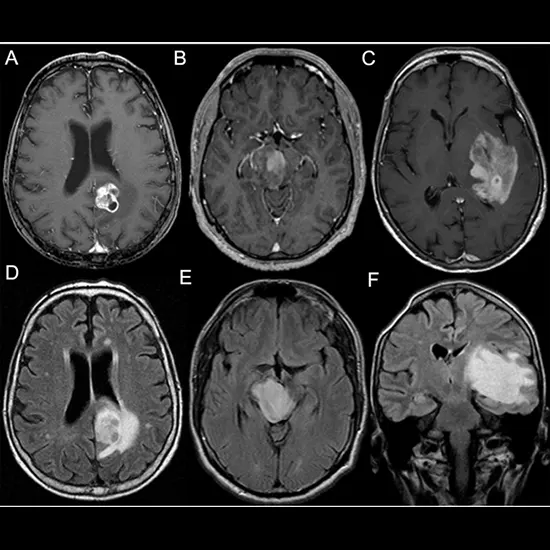

Cerebral astrocytoma is a type of brain tumor that originates from astrocytes, which are glial cells in the cerebral hemisphere of the brain. The cerebral hemisphere is responsible for various functions such as sensory perception, motor control, speech, and cognition. Cerebral astrocytomas are classified as a type of glioma, as they arise from glial cells.

Cerebral astrocytomas can occur in both children and adults, and they can be classified into different grades based on their aggressiveness and appearance under a microscope, according to the World Health Organization (WHO) grading system. Grades of cerebral astrocytomas include grade I (pilocytic astrocytoma), grade II (diffuse astrocytoma), grade III (anaplastic astrocytoma), and grade IV (glioblastoma).

Diagnosis is typically made through imaging studies such as magnetic resonance imaging (MRI) or computed tomography (CT) scans, followed by a biopsy to confirm the tumor type.